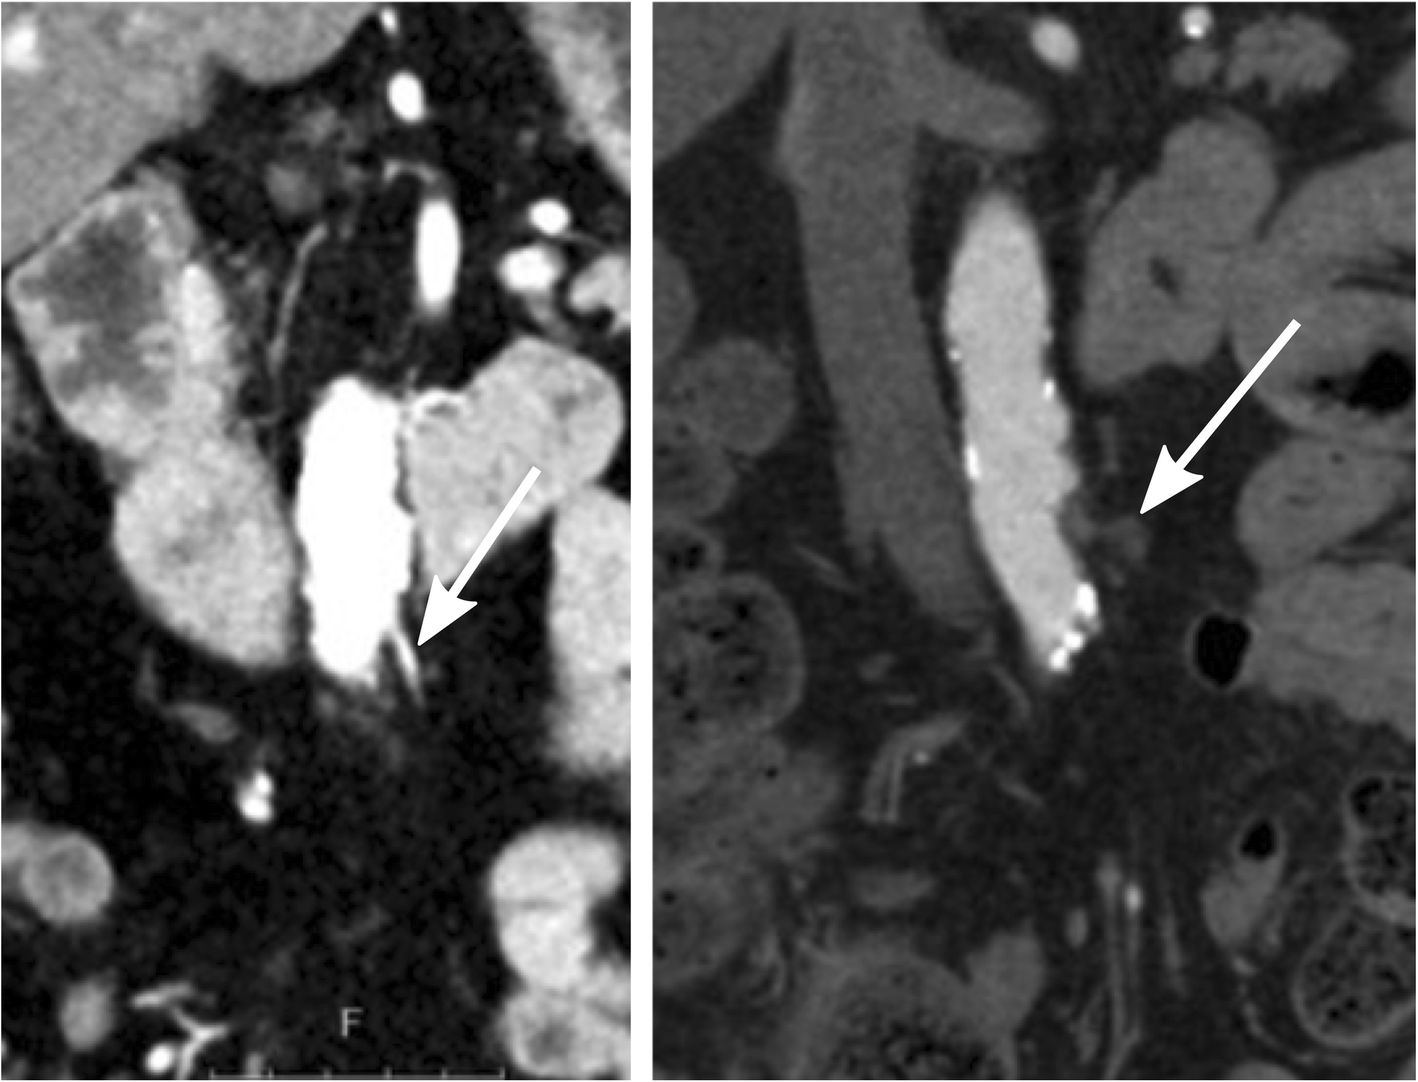

Fig. 2

High ligation level where the inferior mesenteric artery preoperatively can be seen (the image to the left) and postoperatively where it cannot be found (the image to the right). The arrow in the postoperative image to the right demonstrates typical postoperative changes following division of the inferior mesenteric artery close to the aorta